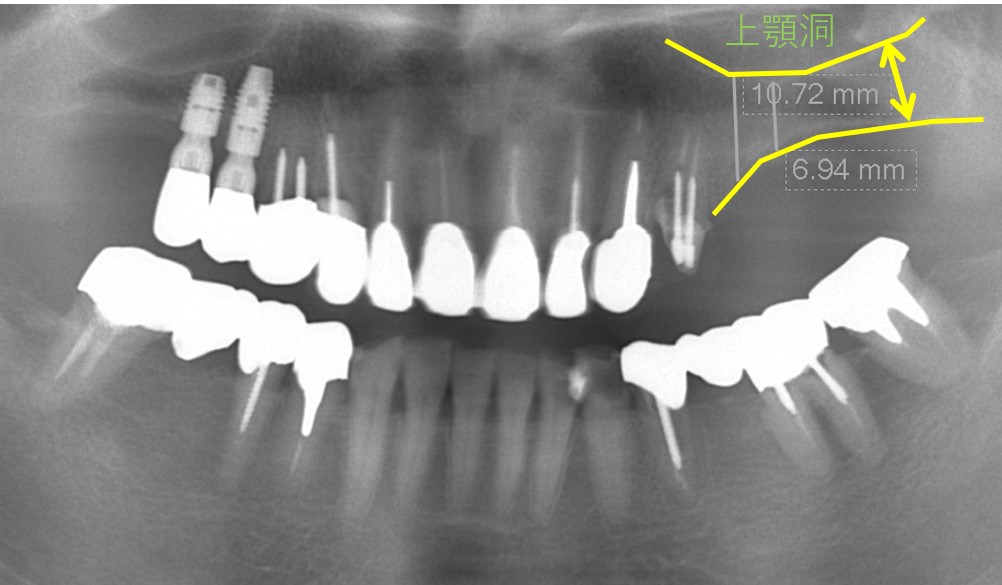

赤○部分は以前埋入したインプラントです。今回、青○部分の欠損部にインプラントを計画しています。

上顎には上顎洞という空洞があるため、黄色矢印の範囲内(骨がある部分)にインプラントを埋入する必要があります。骨を造成する方法もありますが、今回はこの範囲で2本のインプラントを埋入する予定としました。1本は10,72mmの骨幅に、もう1本は6.94mmの骨幅に埋入しなければならないため、9mmと6mmのインプラントを使用することにしました。

インプラント埋入直後の写真です。限られた骨幅にインプラントを埋入できています。